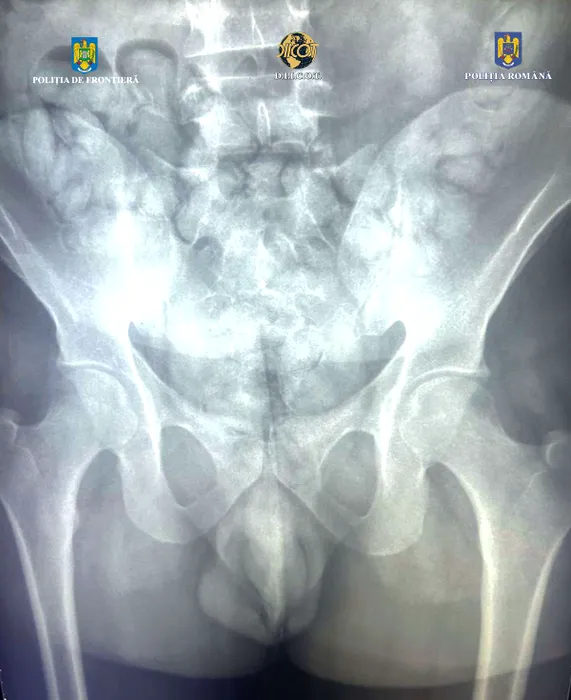

GALERIE FOTO: Un tânăr brazilian a fost prins cu COCAINĂ pe Aeroportul Otopeni. Unde ascundea drogurile și ce cantitate avea asupra sa